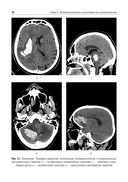

Учебное пособие составлено на основе действующих клинических рекомендаций. Представлены принципы формализованного подхода и формализованные шаблоны протоколов рентгеновской компьютерной томографии и магнитно-резонансной томографии при остром нарушении мозгового кровообращения и нетравматических внутричерепных кровоизлияниях.